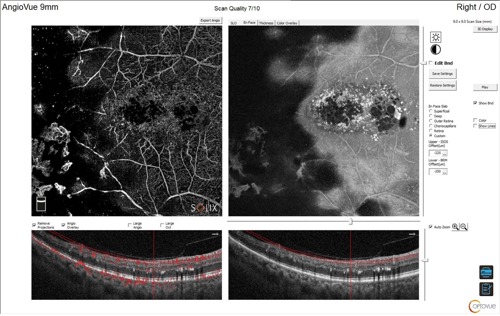

Optical coherence tomography (OCT) and OCT angiography (OCT-A) were performed using the Optovue Solix Spectral Domain OCT system (Visionix) to assess for the presence of neovascularization and macular edema. Due to the equatorial location of the anomalous vasculature, 9x9 mm and 12x12 mm OCT-A were selected.

The utilization of OCT-A was instrumental in confirming the diagnosis of proliferative diabetic and sickle cell retinopathy and identifying associated macular edema. Employing advanced imaging technologies enhances diagnostic accuracy and supports improved clinical decision-making.